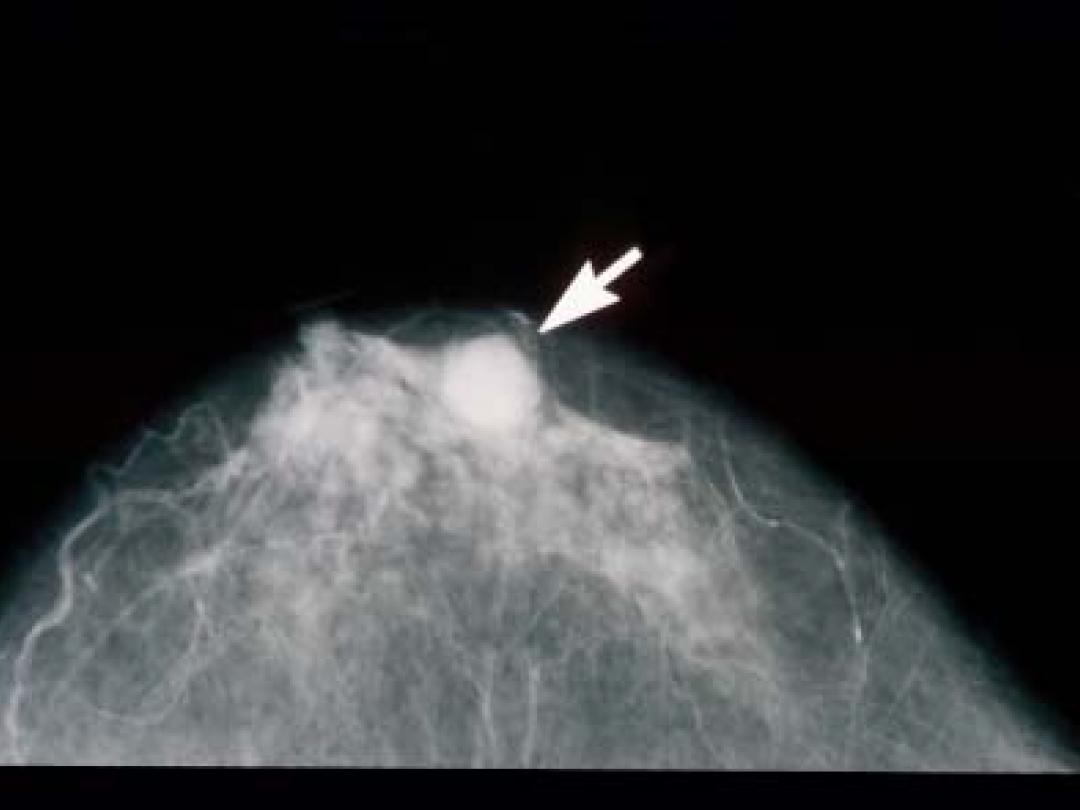

Vorige maand meldde het Erasmus MC in een nieuwsbericht dat de VS de Nederlandse richtlijnen voor borstkankeronderzoek overneemt. Aanleiding voor dat bericht was de publicatie van nieuwe richtlijnen door de US Preventive Services Task Force (USPSTF). Aan die richtlijnen hebben ook onderzoekers van het Erasmus MC meegewerkt. De USPSTF publiceerde…